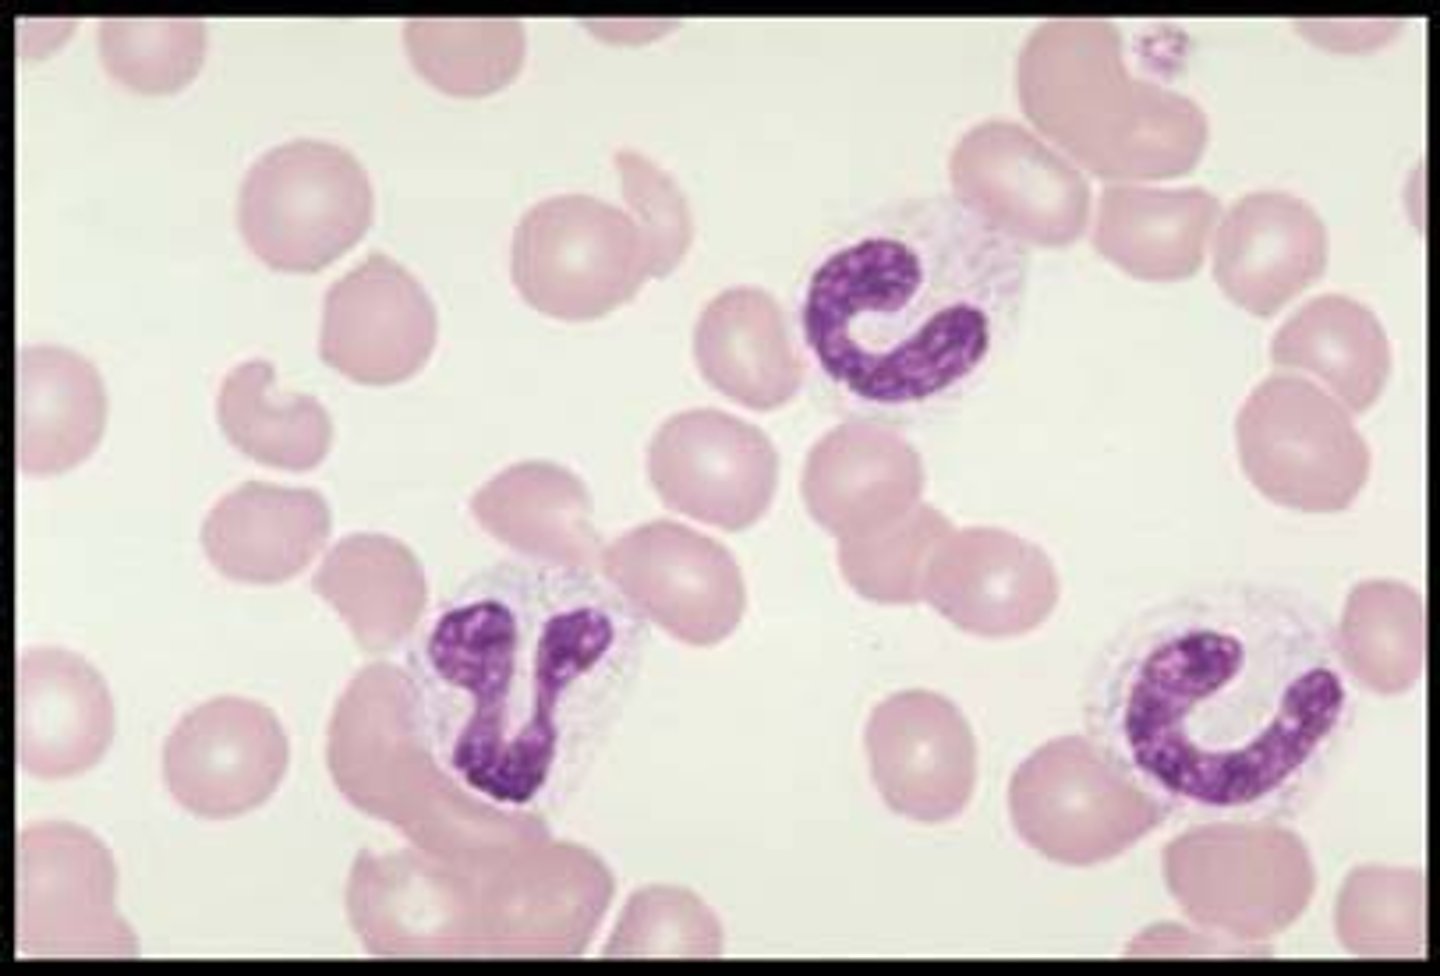

band neutrophils

MAMMAL

incomplete segmentation of nucleus (c-shape)

- pale-blue/purple-dark cytoplasm